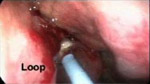

手術圖例-耳鼻喉科手術圖例

• EE229A使用圖例EE229A使用圖例